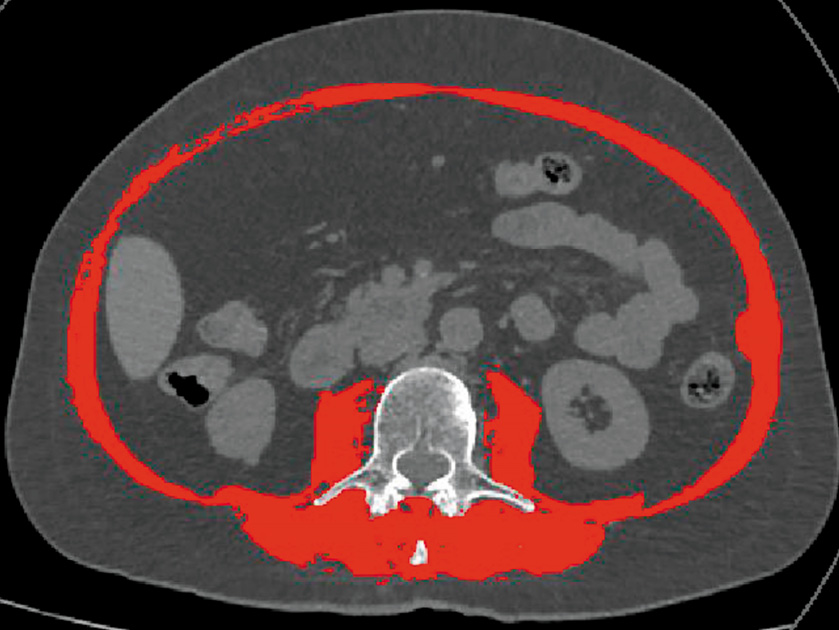

Из сопутствующих заболеваний обращало на себя внимание наличие бронхиальной астмы (неаллергическая форма, легкое персистирующее течение, дыхательная недостаточность 0), гипертонической болезни I стадии 1-й степени, а также астеноневротического синдрома. Пациентка наблюдалась у психиатра в связи с наличием недифференцированного соматоформного расстройства, по поводу которого ежедневно получала флуоксетин (20 мг), оланзапин (10 мг). Потеря массы тела за предшествовавшие 6 мес превысила 28% от исходной, что соответствует наличию у пациентки кахексии. Оценено функциональное состояние: по данным динамометрии сила захвата доминантной руки составила 31 кг, недоминантной – 28,5 кг (пороговое значение для саркопении <16 кг для женщин), тест ходьбы на 400 м – 05 мин 51 с (пороговое значение – 6 мин). Проведен анализ скелетно-мышечной мускулатуры с помощью компьютерной томографии на уровне III поясничного позвонка (рис. 1). Площадь скелетной мускулатуры составила 106,5 см2, скелетно-мышечный индекс LIII (отношение площади мышц на уровне LIII позвонка к квадрату роста пациента) – 38,3 см2/м2. В соответствии с диагностическими критериями Prado (<38,5 см2/м2 для женщин) и Martin (<41 см2/м2 для женщин) данные результаты можно трактовать как наличие у больной саркопении [7, 8].

Рис. 1. Оценка площади скелетно-мышечной мускулатуры на уровне LIII. / Fig. 1. Assessment of skeletal muscle area at the LIII level.